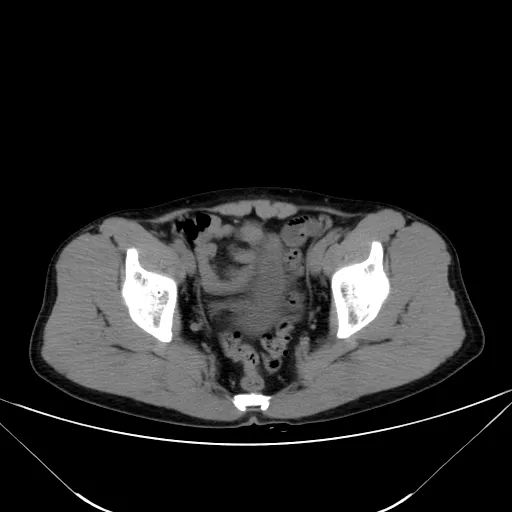

肝脏缩小,包膜凹凸不平,肝裂增宽,各叶比例失衡,肝实质密度不均,肝S4小片低密度影,约cm;胆囊不大,其内未见异常密度影,胆道系统未见扩张;胰腺、脾脏形态、密度、大小未见异常;双肾上腺及双肾形态、密度、大小未见异常,双输尿管未见扩张,膀胱充盈良好,壁光滑,其内未见异常密度影;前列腺未见异常;胃肠道未见充盈,壁未见明确增厚,食管胃底多发迂曲、增粗血管,腹部及腹膜后未见肿大淋巴结;腹水。